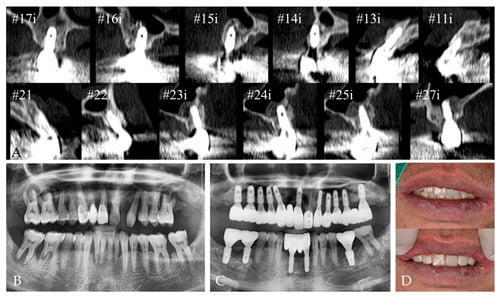

2. Case Report